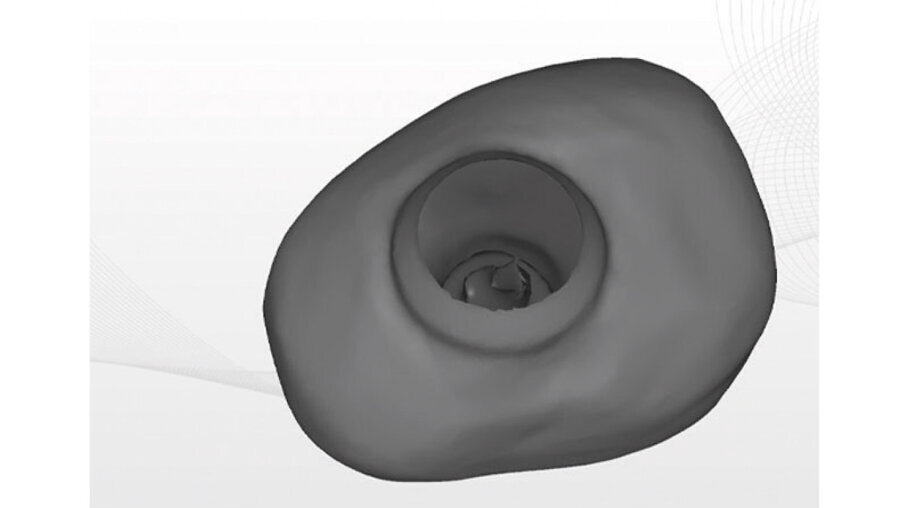

La vite di guarigione è stata costruita con tecnica CAM mediante fresatore 5X a partire da un blocchetto riempito di Polimetilmetacrilato (PMMA), con residuo di monomero inferiore allo 0,02%. La progettazione CAD è stata fatta con apposito software exocad (Figg. 8a-8c). L’impronta pre-operatoria e intra-operatoria sono state confrontate per ottenere il progetto della vite. L’impronta pre-operatoria del dente da estrarre è stata utilizzata come base per la forma del provvisorio. L’unica modifica apportata è stata quella di abbassare il piano occlusale in modo che la vite non interferisse con i carichi. L’impronta intra-operatoria invece è stata usata per ottenere la corretta posizione dell’impianto.

Figg. 8a-8c_Progettazione CAD della vite di guarigione customizzata.